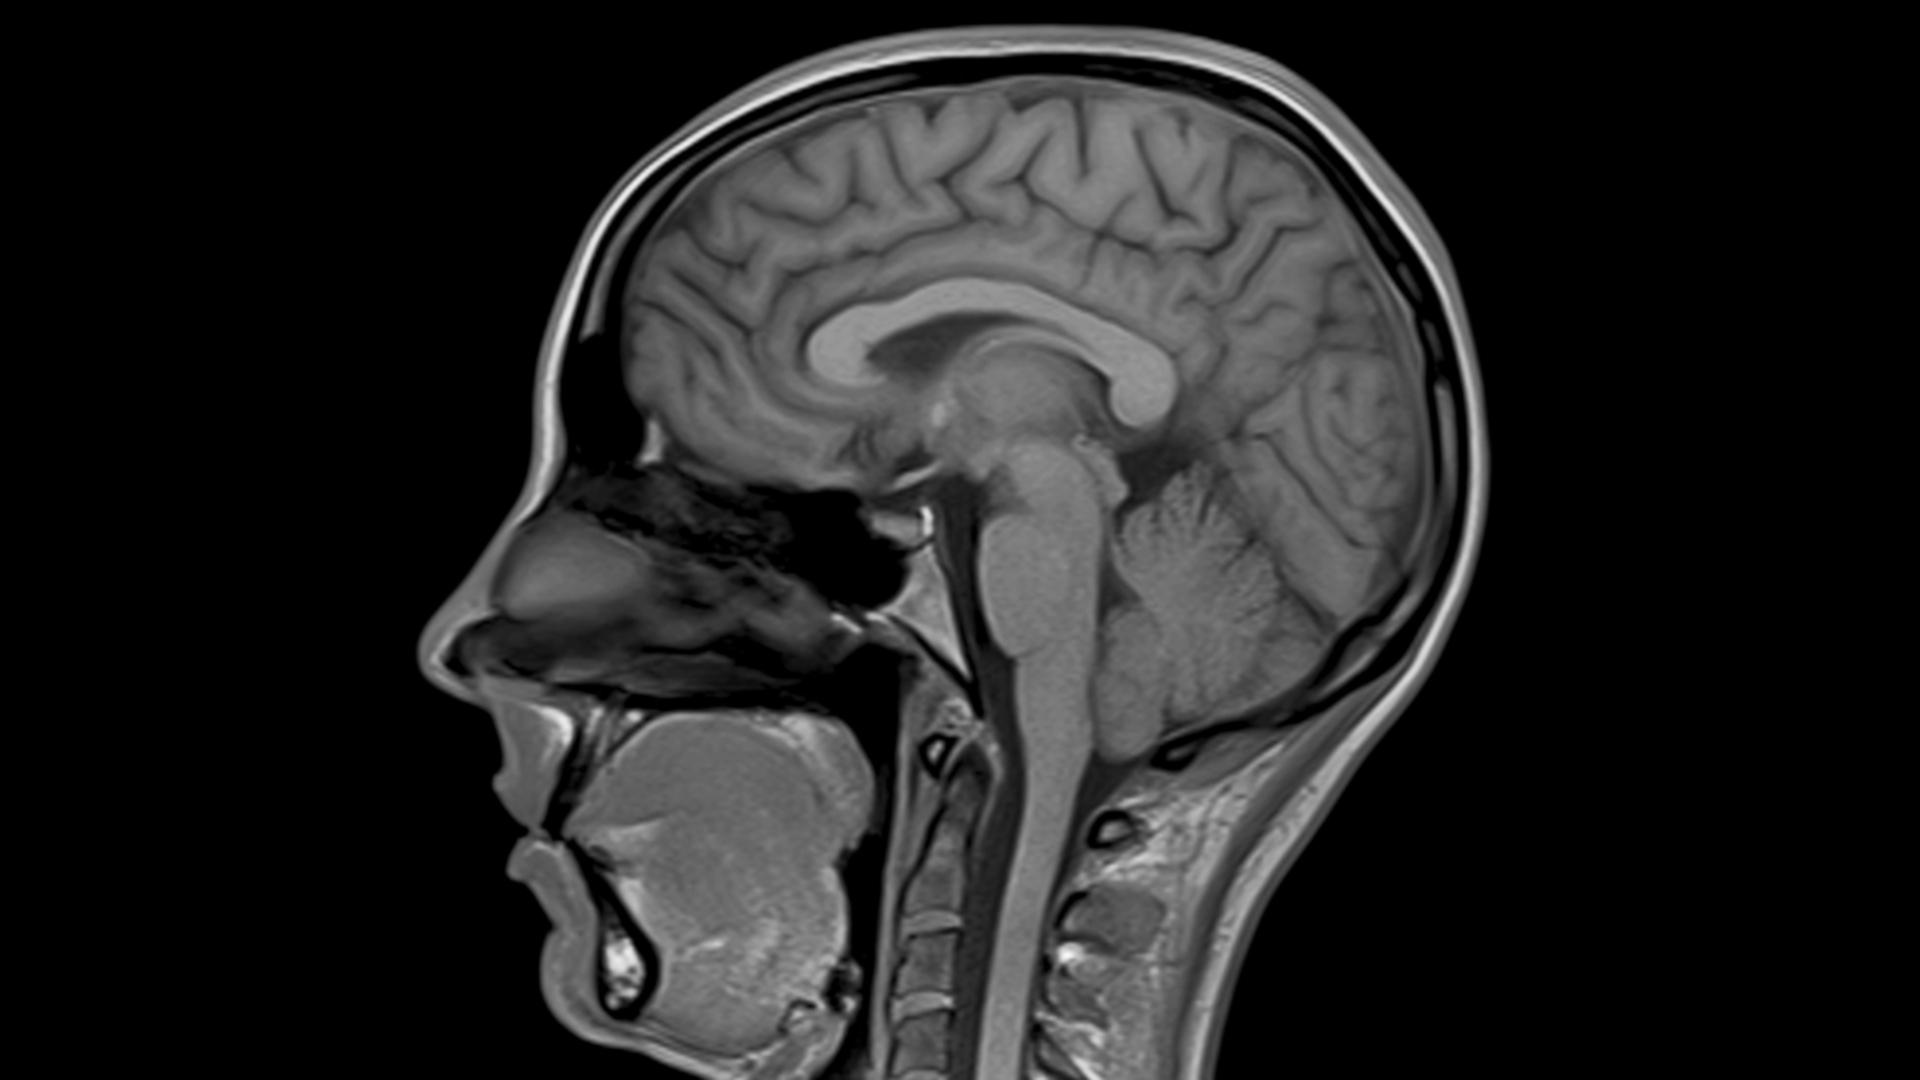

MAGNETOM® Skyra is the world's first 3 Tesla, 70 cm Open Bore Tim+Dot system By combining our pioneering deep learning image reconstruction technology Boost with our acclaimed acceleration techniques, MAGNETOM Skyra Fit achieves acceleration of up to 88%.

MAGNETOM Skyra's Onco Suite features a collection of sequences, protocols, and evaluation tools that guide users through the detailed assessment of a variety of oncological conditions. View and Download Siemens MAGNETOM Skyra owner's manual online Through the integration of groundbreaking Tim® 4G (Total imaging matrix) and DotTM (Day optimizing throughput), MAGNETOM Skyra sets a new standard of efficiency, ease of use, and care, which will help harness a new level of productivity

Buy Used Very Good SIEMENS Skyra 3T Online ⭐. Siemens Skyra 3T The Siemens MAGNETOM Skyra 3T is the world's first 70cm TIM 4G + DOT 3 Tesla strength MRI system with the smallest footprint of any 3T system currently on the market Through the integration of groundbreaking Tim® 4G (Total imaging matrix) and DotTM (Day optimizing throughput), MAGNETOM Skyra sets a new standard of efficiency, ease of use, and care, which will help harness a new level of productivity